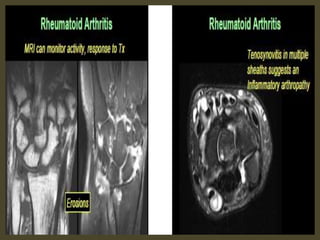

Tenosynovitis in a 32-year-old woman with early

rheumatoid arthritis of the wrist (5 months duration)

and normal radiographic findings. Axial T1-weighted

(a), fat-suppressed T2-weighted (b), and contrast-

enhanced fat-suppressed T1-weighted (c) MR images

show marked tenosynovitis (arrows) involving both

the dorsal extensor and volar flexor compartments.

Note that the tenosynovitis and periscaphoid joint

synovitis (*) have the same signal intensity in a

(intermediate) and b (high) and similar enhancement